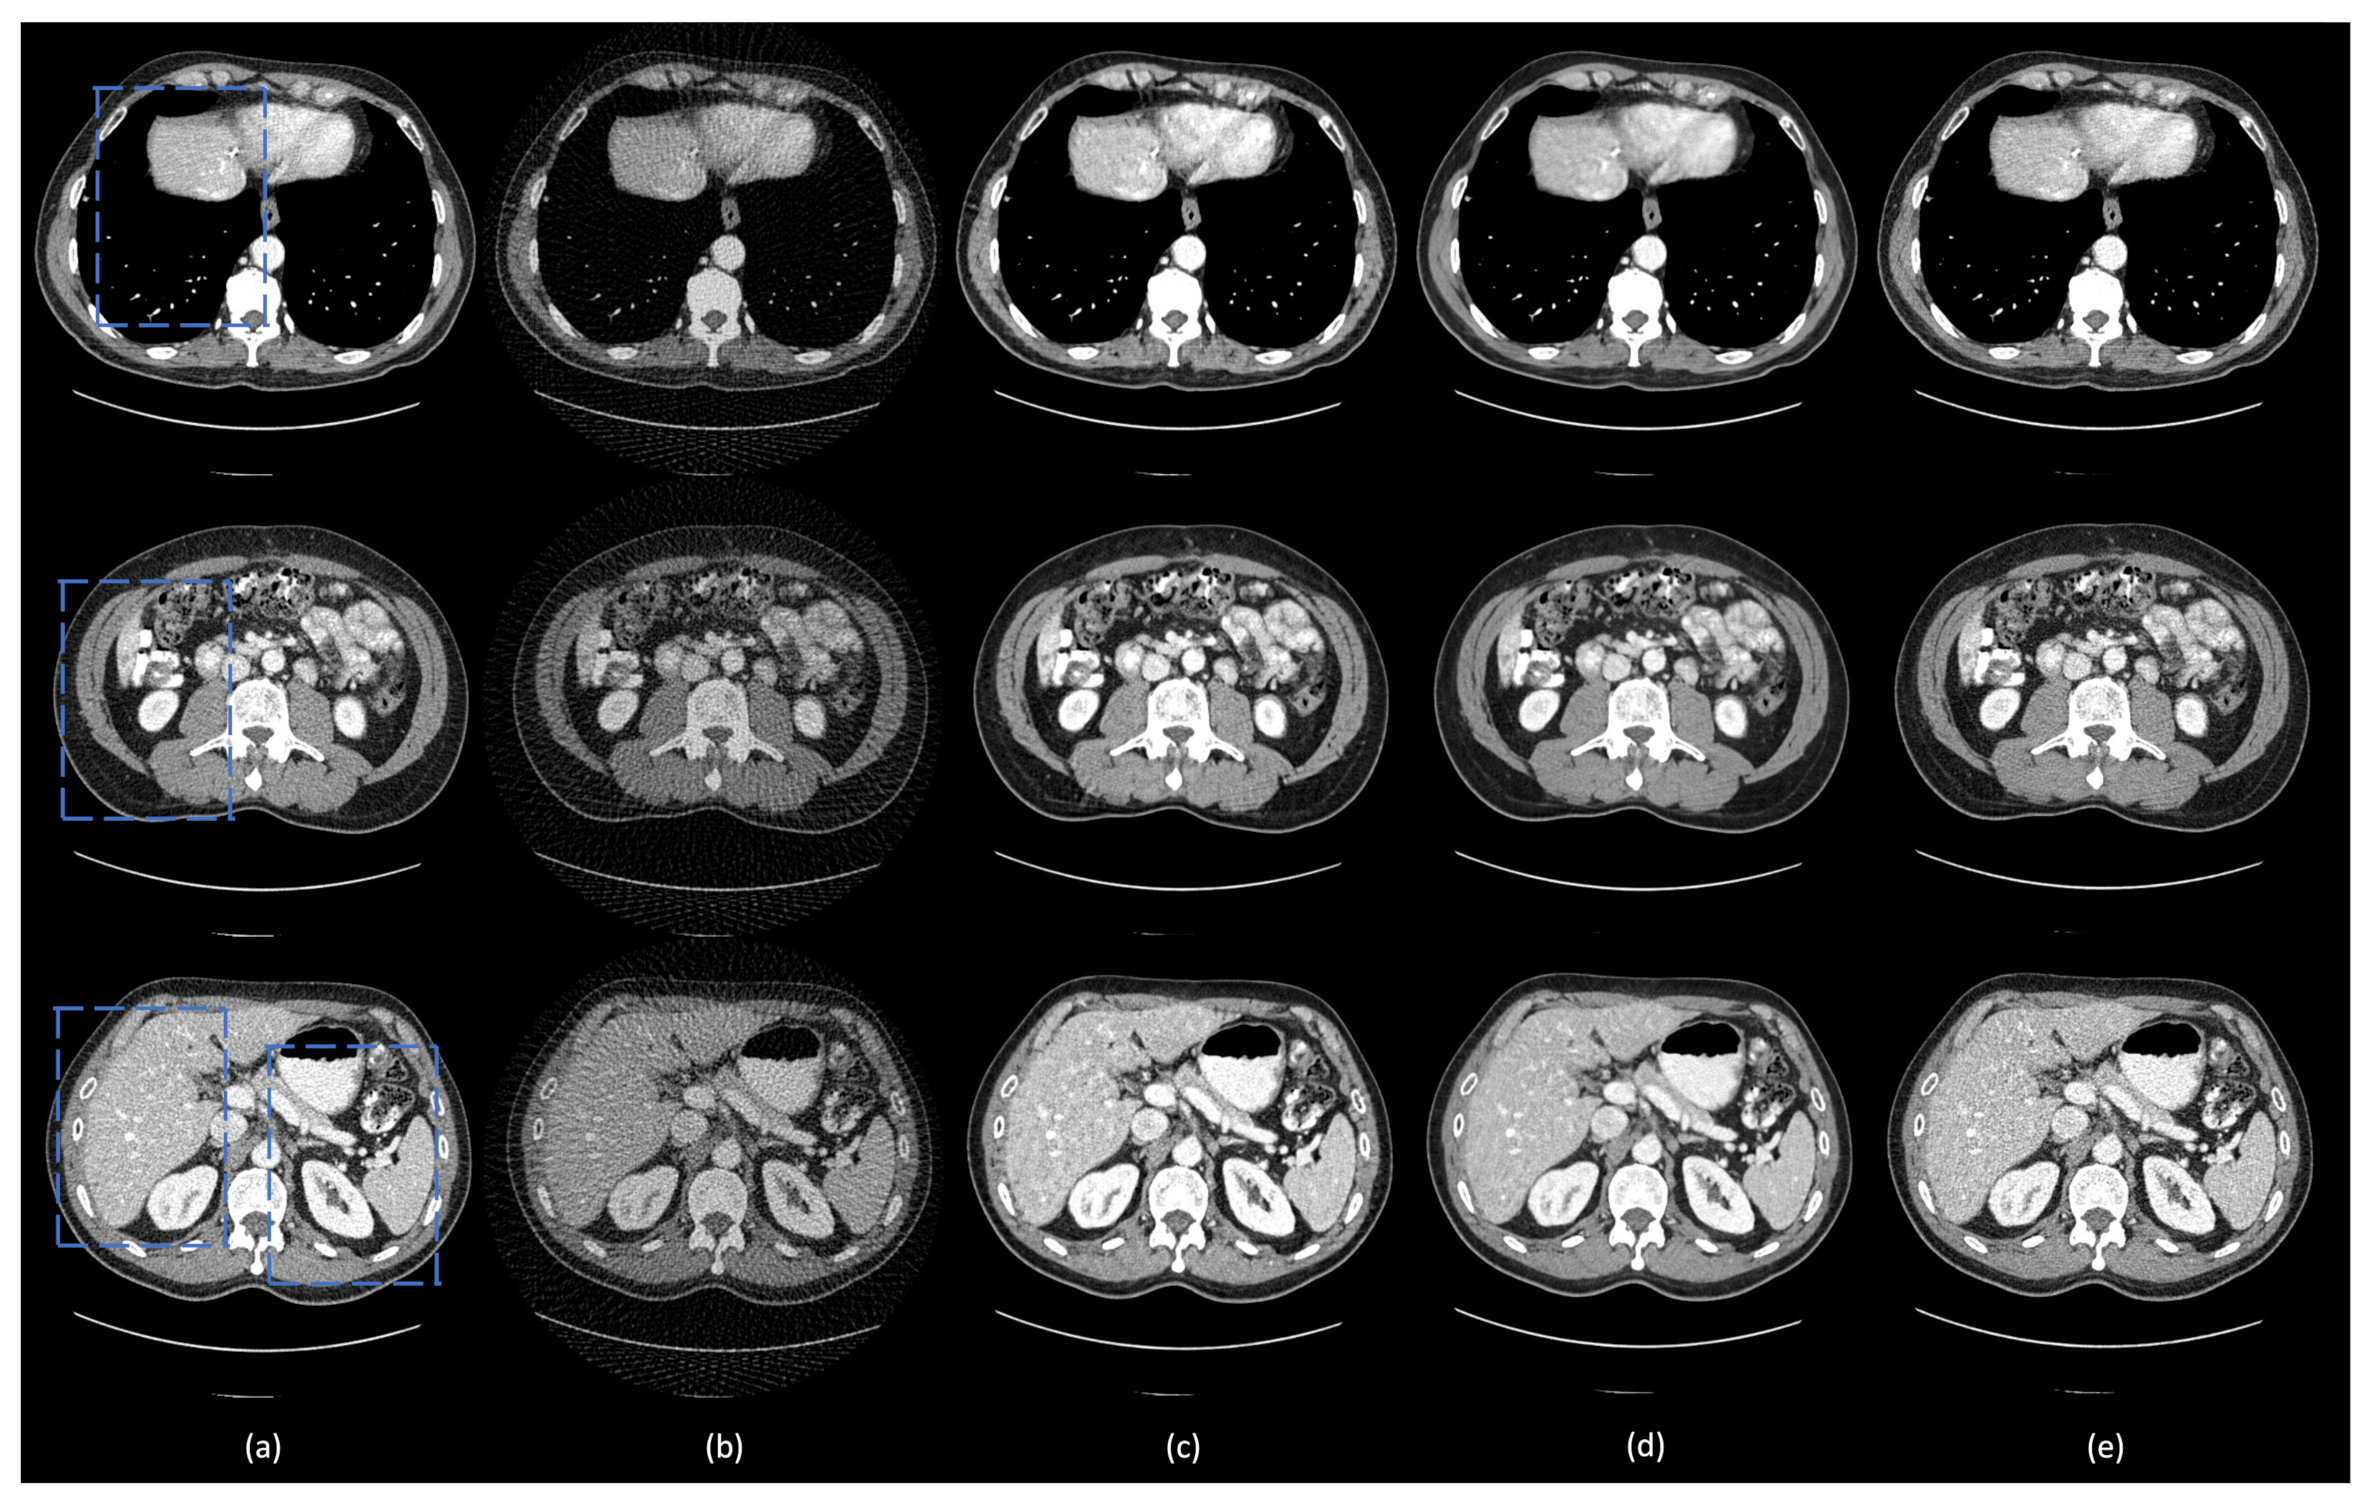

3.2. Hyperparameter Selection and Network Comparison

3.3. Comparison with Other Deep Learning Methods